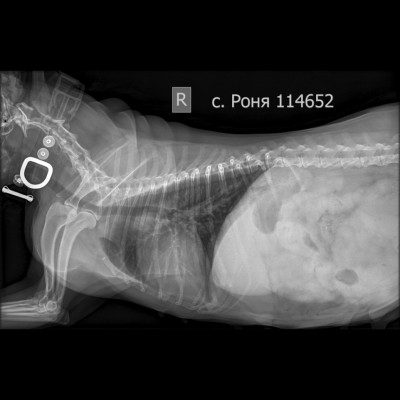

Москва, цвергшнауцер Роня, 6 лет

Рентген в двух проекциях и бак посев из раны